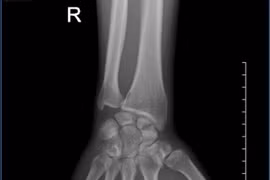

Gãy xương thuyền cần được quan tâm đúng mức, tránh bỏ sót thương tổn, có chỉ định can thiệp đúng và hợp lý để tránh bỏ sót, tạo khớp giả, viêm khớp dẫn đến hạn chế vận động cổ tay.